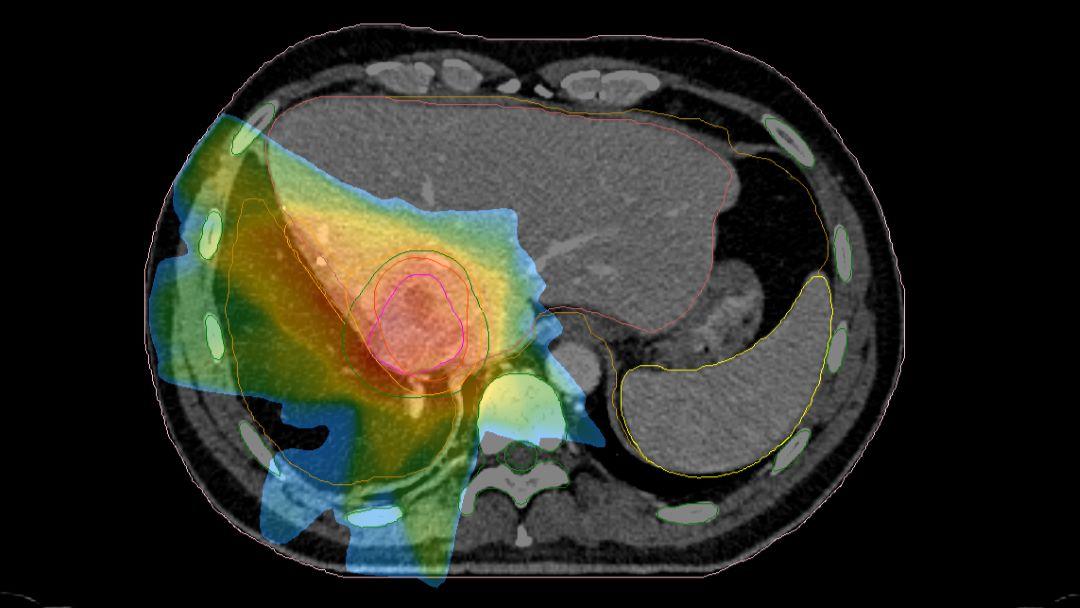

Radiation oncology image showing colour-coded organs at risk

Radiation therapy is a treatment that uses ionizing radiation to either kill malignant cancer cells or at least control their growth. The most common type of radiation therapy is external-beam radiation therapy that is normally delivered using a linear accelerator. The aim of radiation therapy is to treat cancer without damaging healthy cells as much as possible. It can be used in combination with other cancer treatments, such as chemotherapy or surgery.